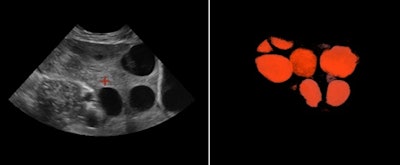

In reproductive medicine, the ovaries are measured to detect abnormalities. Ovarian size can be determined by measuring the ovary in three dimensions (width, length, and depth) on views in two orthogonal planes or by visualizing a 3D volume, according to the 2008 AIUM practice parameter "Ultrasound in Reproductive Medicine."